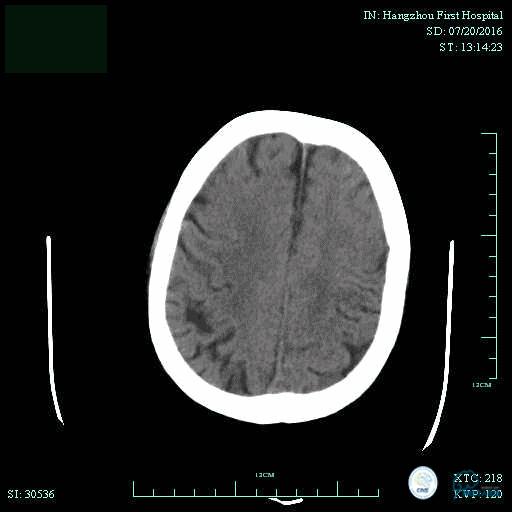

辅助检查:血常规、生化、凝血功能未见明显异常,心电图:窦性心律,ST-T改变;头颅CT平扫:未见明显出血。头颅MRI:未见新鲜梗塞灶;头颅MRA:双侧大脑前动脉远端缺如。

术前头颅CT平扫。

术后头颅CT复查。

术后第二天患者意识清,言语清,右上肢肌力1级,右下肢肌力3级,左上肢肌力5级,左下肢3级。

术后90天随访右上肢肌力3级,左上肢肌力5级,双下肢肌力4级,mRS评分3分。